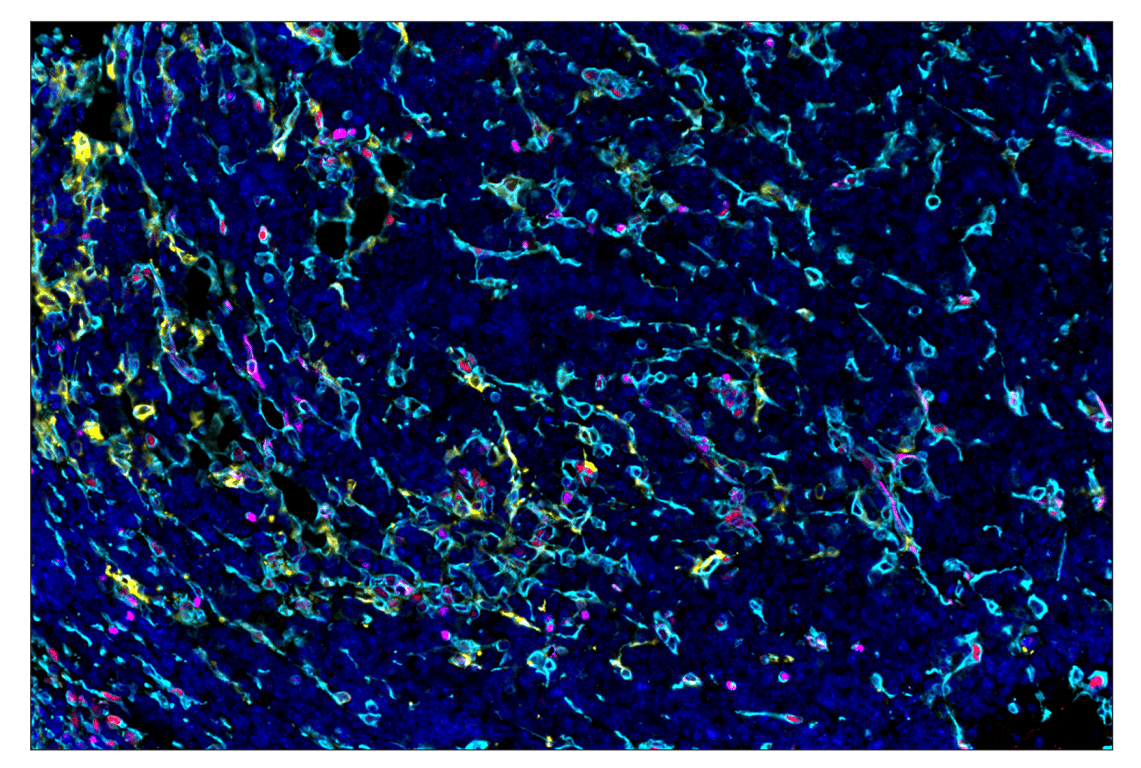

SignalStar™ multiplex immunohistochemical analysis of paraffin-embedded GL261 syngeneic tumor using Phospho-SLP-76 (Ser376) (E3G9U) & CO-0018-594 SignalStar™ Oligo-Antibody Pair #53299 (yellow), Phospho-Stat3 (Tyr705) (D3A7) & CO-0029-647 SignalStar™ Oligo-Antibody Pair #94459 (red), Vimentin (D21H3) & CO-0012-750 SignalStar™ Oligo-Antibody Pair #61002 (cyan), and DAPI #4083 (blue). All fluorophores have been assigned a pseudocolor, as indicated. Staining was performed on the BOND RX autostainer by Leica Biosystems.

Immunohistochemistry Image 6: Phospho-Stat3 (Tyr705) (D3A7) & CO-0029-488 SignalStar<sup>™</sup> Oligo-Antibody Pair